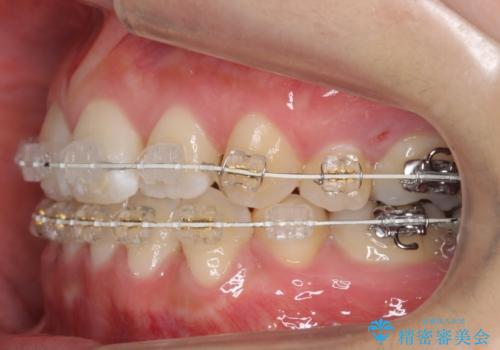

- 矯正装置

- ワイヤー矯正

治療の後半に地方に転居され、2か月に一回の調整となり結果、治療期間がかかりました。

通院はしっかりしていただいたため、無事終了することができました。